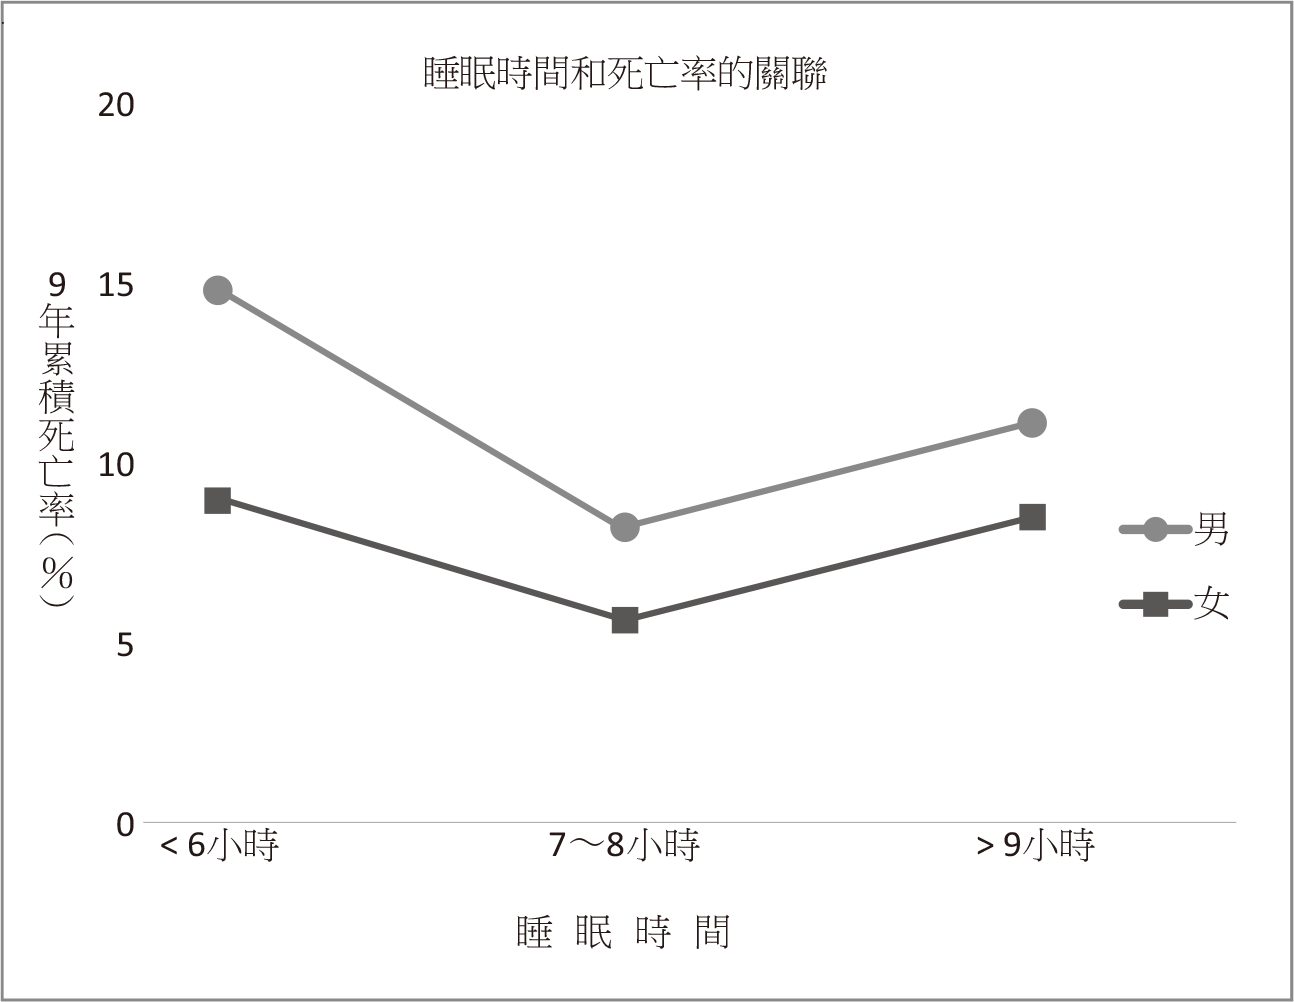

後來到了1983年,科學家才提出分析,探討性別、睡眠時間和死亡率的關係。我在這裡特別做成圖表,讓你可以看得更清楚。

就像右頁這張圖所顯示的,無論男女,睡眠時間在7~8小時的組,9年累積死亡率是最低。然而,如果睡不到6小時,死亡率就提高了。

舉例來說,睡眠時間在7~8小時的男性,9年的累積死亡率是8.2%,但睡眠不足6小時的死亡率則接近14.8%。睡眠時間在7~8小時的女性,9年死亡率是5.6%,而睡不夠6小時的女性,死亡率可以達到9.0%。

當然,這樣的結果,還符合我們一般的預期——睡得不夠,也就不健康,甚至可能影響壽命。但是,出乎意料的是,無論男女,睡眠超過9小時的組,反而死亡率還比睡7~8小時的更高。

經牛津大學出版社(Oxford University Press)許可,重製自Wingard DL et al. (1983) Mortality risk associated with sleeping patterns among adults. Sleep 6: 102—7.